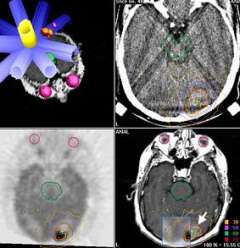

Stereotactic radiosurgery: The upper left image shows a treatment plan in which beams of radiation (in blue) are all directed at a tumor target at various angles around an arc. The diameter of each beam is based on the cross-sectional size of the tumor from that direction. Note that certain radiation sensitive structures do not have radiation passing through them, including the brainstem (green) and eyes (lavender). The other three images (upper right, CT; lower left, PET; and lower right, MRI), show how UCLA doctors can use imaging information from many different types of advanced diagnostic imaging machines for the best treatment planning of this target (arrow).